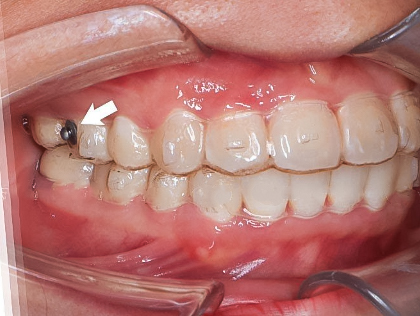

Button chỉnh nha là các nút nhỏ được gắn lên trên mặt răng bằng keo nha khoa chuyên dụng. Một số trường hợp bác sĩ sử dụng button như hạt mắc cài có thể gắn mặt trong hoặc ngoài của răng. Button được thiết kế có phần đầu nút button dễ dàng gắn thun với nhiều kích thước khác nhau và phần mặt gắn vào răng lõm, cong, có các vân để bác sĩ thao tác, gắn lên răng chắc chắn hơn.

Phần lõm trên mặt nút cũng giúp bác sĩ xác định đúng vị trí cần gắn, dễ điều chỉnh nếu cần. Button chỉnh nha là một khí cụ nha khoa có thể đặt ở nhiều vị trí răng khác nhau và có thể sử dụng cho cả phương pháp niềng răng mắc cài hay khay niềng trong suốt. Tuy vậy, không phải trường hợp nào cũng cần sử dụng button khi chỉnh nha.

Một số tình trạng bác sĩ tại Tâm Thiện Mỹ sẽ sử dụng button chỉnh nha thay cho một số mắc cài để điều chỉnh răng xoay, mọc kẹt, không gắn được mắc cài về đúng vị trí trên cung hàm mà không ảnh hưởng quá trình niềng răng, kế hoạch ban đầu của bác sĩ đưa ra. Sau khi gắn button niềng răng bác sĩ có thể mắc thêm dây chun để tạo lực tác động giúp răng được chỉnh về đúng vị trí mong muốn hiệu quả nhất.